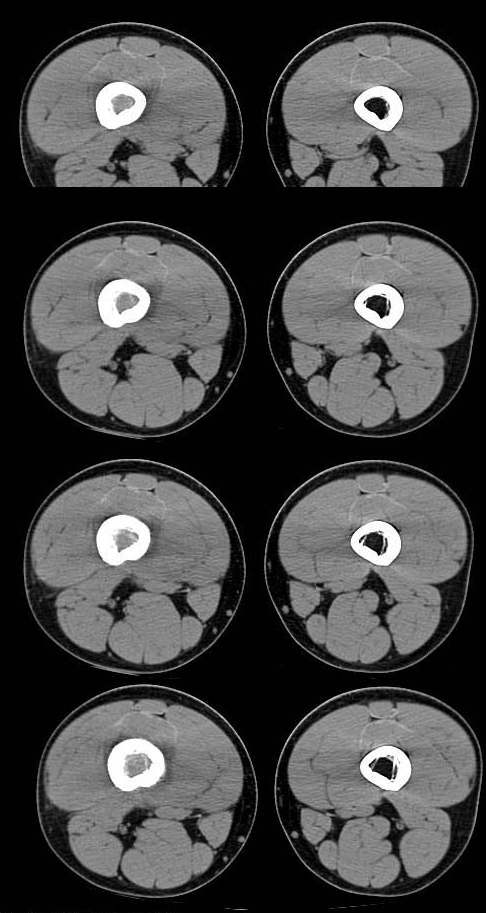

20岁,男,右股骨下端疼痛一个月,无发热,白细胞正常,皮肤不红,肿胀,触痛。

右股骨下端很长范围内的髓腔扩大,骨小梁破坏消失,皮质亦呈融骨性破坏,周围脂肪层次紊乱,肌肉受累及密度减低。考虑为:恶性骨肿瘤。请专家们分析骨肉瘤及尤文氏肉瘤的ct征象。

6.ct及mri:能较好地判断肿瘤的范围及侵犯软组织的情况。mri可见瘤体处广泛性骨质破坏,呈软组织肿块影;在t1加权像上呈均匀的长t1信号;在t2加权像上呈很长t2高信号。在ct上显示为源于骨组织的软组织肿块,骨质广泛破坏。

长骨ct见的较少,该病例股骨下端表现为边缘模糊的溶骨性破坏,伴有费用性脱钙,髓腔密度增高,呈毛玻璃样改变,病变周围软组织肿胀,脂肪间隙模糊,无骨膜反应,应密切结合临床,考虑骨纤维肉瘤或慢性骨脓肿。期待结果。

此病例基本可定是恶性骨肿瘤:髓腔内长范围肿块、皮质不规则破坏、软块及软组织浸润、瘤骨及不规则骨膜反应等。可以肯定地除外炎性病变和骨纤。

结合临床还是将尤文氏肉瘤放在前面,骨肉瘤不排除。纤维肉瘤及恶纤组多见老年人,不放在首要诊断范围内。